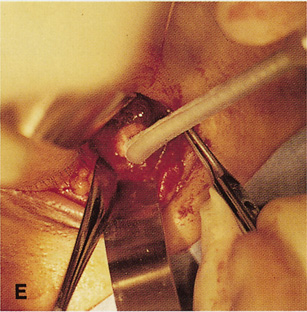

Fig. 6. Lateral orbitotomy through upper eyelid skin crease A. Photo demonstrating right globe ptosis present for more than 2 years. B. Axial CT scan showing a well outlined oval lesion in the lacrimal gland

fossa. C. Coronal CT showing lesion pushing globe inferiorly. D. Skin crease excision marked for lateral orbitotomy. E. Lateral orbital rim exposed. Bone cuts made above frontozygomatic suture

and at zygomatic arch. F. Lateral wall removed. Subperiosteal space exposed. Hard tumor could be

palpated in area of lacrimal gland. G. Benign mixed tumor of lacrimal gland removed. H. Bone sutured into place. I. Skin crease closed. |

zygomatic arch, which is even with the orbital floor (see Fig. 6E). Once the outer surface of the lateral rim has been exposed, the periorbita